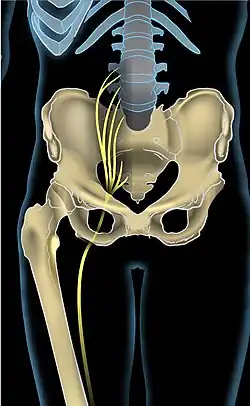

Iskiasnerven (Latin: nervus ischiadicus [1]) er navnet på den største nerve, mennesket har. Nerven udspringer fra plexus sacralis, går ned gennem benene, for endeligt at forgrene sig til læg og fod. Denne nerve er blandt andet ansvarlig for følesansen og motorisk innervation af muskulaturen i underekstremiteten. [2] Iskias er ofte refereret til som smerter i dette område. Smerter, der ofte trækker fra lænd og sæderegion ned i benet, tit bag på låret, i knæhasen, læg, hæl og eventuelt videre ud i foden, eksempelvis til storetåen. Dette er dog et smertebillede, som typisk involverer nerverodspåvirkning, eksempelvis forårsaget af en diskusprolaps, der trykker på en eller flere nerverødder. Smerterne er altså ikke altid kun karakteriseret til iskiasnerven, men involverer flere nerver i plexus sacralis; som beskrevet ovenfor vil smerter svarende til iskiasnerven manifestere sig til de distale regioner af underekstremiteten.

Iskiassmerter opleves som smerter, følelsesløshed eller prikken der kommer til udtryk både i lænd og længere ned gennem balder og ben. Disse smerter skyldes, at iskiasnerven bliver trykket eller klemt af enten skelettet eller af den omkringliggende muskulatur. Disse smerter opleves oftest kun i det ene ben og forværres, når man sidder, end når man står op, grundet yderligere komprimering af de involverede strukturer i siddende stilling.[3]